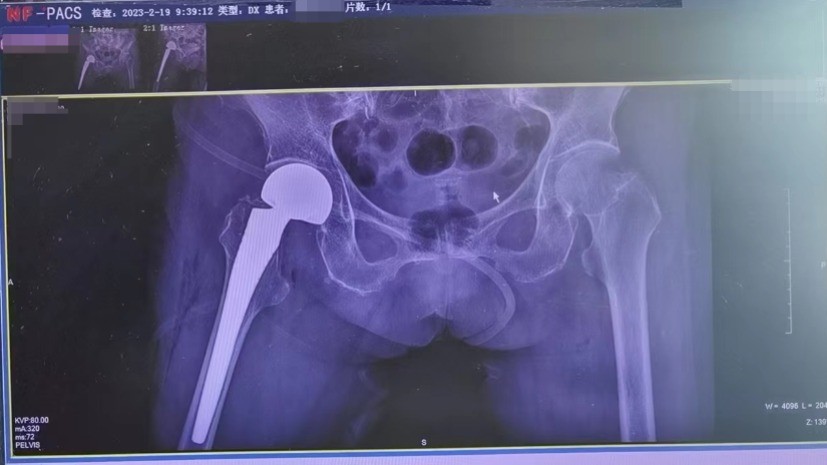

术后DR片

术后第一天早上,黎主任查房看到刘奶奶精神状态良好,髋关节疼痛明显缓解,她说:“昨晚睡了个好觉,今早胃口也好了。”复查显示假体位置良好,经过评估刘奶奶身体条件后,医生及家属共同协助她术后首次下床。刘奶奶步态良好,行走稳定。家属激动地说道:“没想过老人家这个岁数居然还能做手术,更没有想到术后这么早就能下床活动了,太感谢医护人员了!”